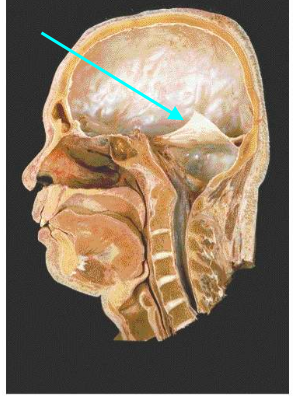

Which dural fold is the arrow pointing to

Tentorium cerebelli

Tentorial notch

Falx cerebelli

A